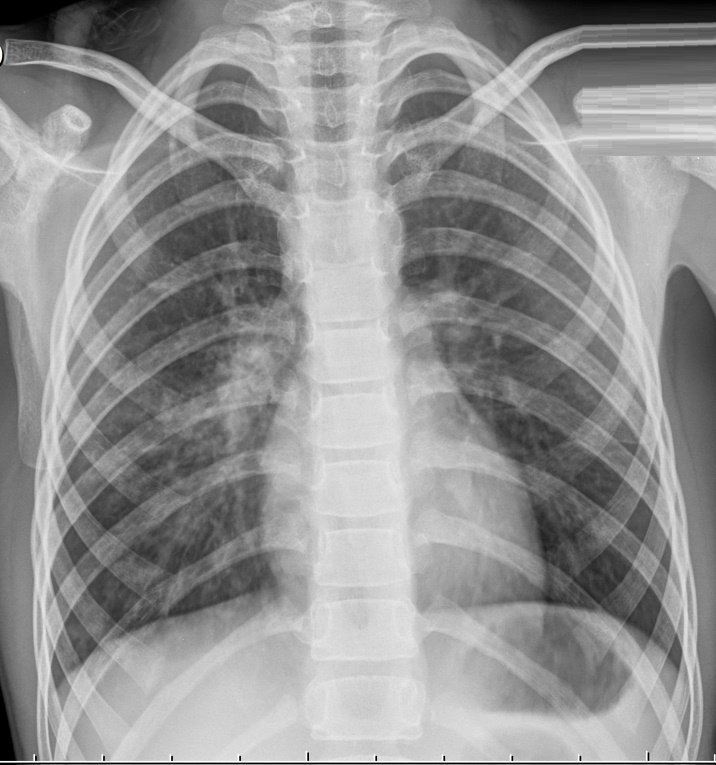

После проведения рентгенографии снимки должен изучить специалист, и на основе полученных данных и результатов других исследований сделать соответствующие выводы и поставить диагноз. В норме легкие и бронхи человека выглядят следующим образом:

- легочные доли имеют одинаковый, равномерный черный оттенок;

- в районе сердца наблюдается белый просвет;

- ребра и ключицы серые, с привычными очертаниями;

- купола диафрагмы белого цвета;

- позвоночный столб расположен в центре.

Признаки пневмонии на рентгеновском снимке во многом зависят от формы заболевания и его стадии, а также от локализации патологического процесса. Если исследование показало признаки пневмонии, необходимо как можно скорее приступить к лечению – запущенный патологический процесс опасен не только для здоровья, но и для жизни человека.

Первый признак пневмонии на рентгеновском снимке – появление очагов затемнения с неровными контурами в разных частях легкого, которые могут иметь разный размер, от 3-4-х до 12 мм.

Тени различают по внешнему виду (круглые, овальные кольцевидные) и интенсивности окраски – чем темнее пятно, тем сильнее выражен патологический процесс.

При поражении лимфатических узлов и нарушении кровоснабжения органа могут наблюдаться изменения корней легких, а если болезнь затронула плевру – нарушение в рисунке куполов диафрагмы. В остальном проявления пневмонии зависят от стадии, формы и клинических особенностей заболевания:

- Очаговая форма. На рентгене отображаются небольшие (1-1,5 см) тени со слабой или умеренной интенсивностью окраски, неоднородной структурой и нечеткими границами. Очаги поражения могут быть единичными или множественными, а в некоторых случаях они сливаются в одно большое пятно. Корни легких расширены, причем нарушения нормального рисунка органа могут сохраняться в течение нескольких дней после выздоровления.

- Крупозная пневмония. Наблюдаются изменения нормального легочного рисунка, жидкость в полости плевры, признаки инфильтрации одной из долей легкого, расширение корней. По мере развития воспалительного процесса выраженность изменений и интенсивность окраски затемнений усиливается.

- Интерстициальная форма. На снимке заметно уплотнение корней легких и другие изменения, которые формируют выраженный рисунок, напоминающий ветви дерева.

- Абсцедирующая пневмония. Проявляется обширным затемнением пораженной области, признаками утолщения плевры и наличием полостей разного размера, наполненных жидкостью.

- Аспирационная форма. Рентген характеризуется треугольными пятнами с однородной структурой, светлыми очагами и приподнятой диафрагмой.

При пневмонии, на рентгеновском снимке легких, видны следующие признаки:

- в разных частях органа находятся очаги затемнения, имеющие неровные контуры и размер 3-12 мм;

- различаются тени по внешнему виду (овальные, кольцевидные, круглые), интенсивности цвета – чем темнее будет пятно, тем сильнее патологический процесс;

- если поражены лимфатические узлы и нарушено кровоснабжение органа, может быть заметно изменение корней лёгких, если поражена плевра – видны нарушения в рисунке куполов диафрагмы.

На рентгеновском снимке пневмония выглядит следующим образом: